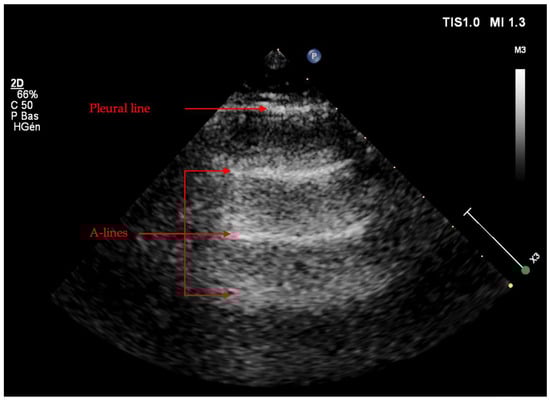

Artifacts

Patterns in the LUS Examination